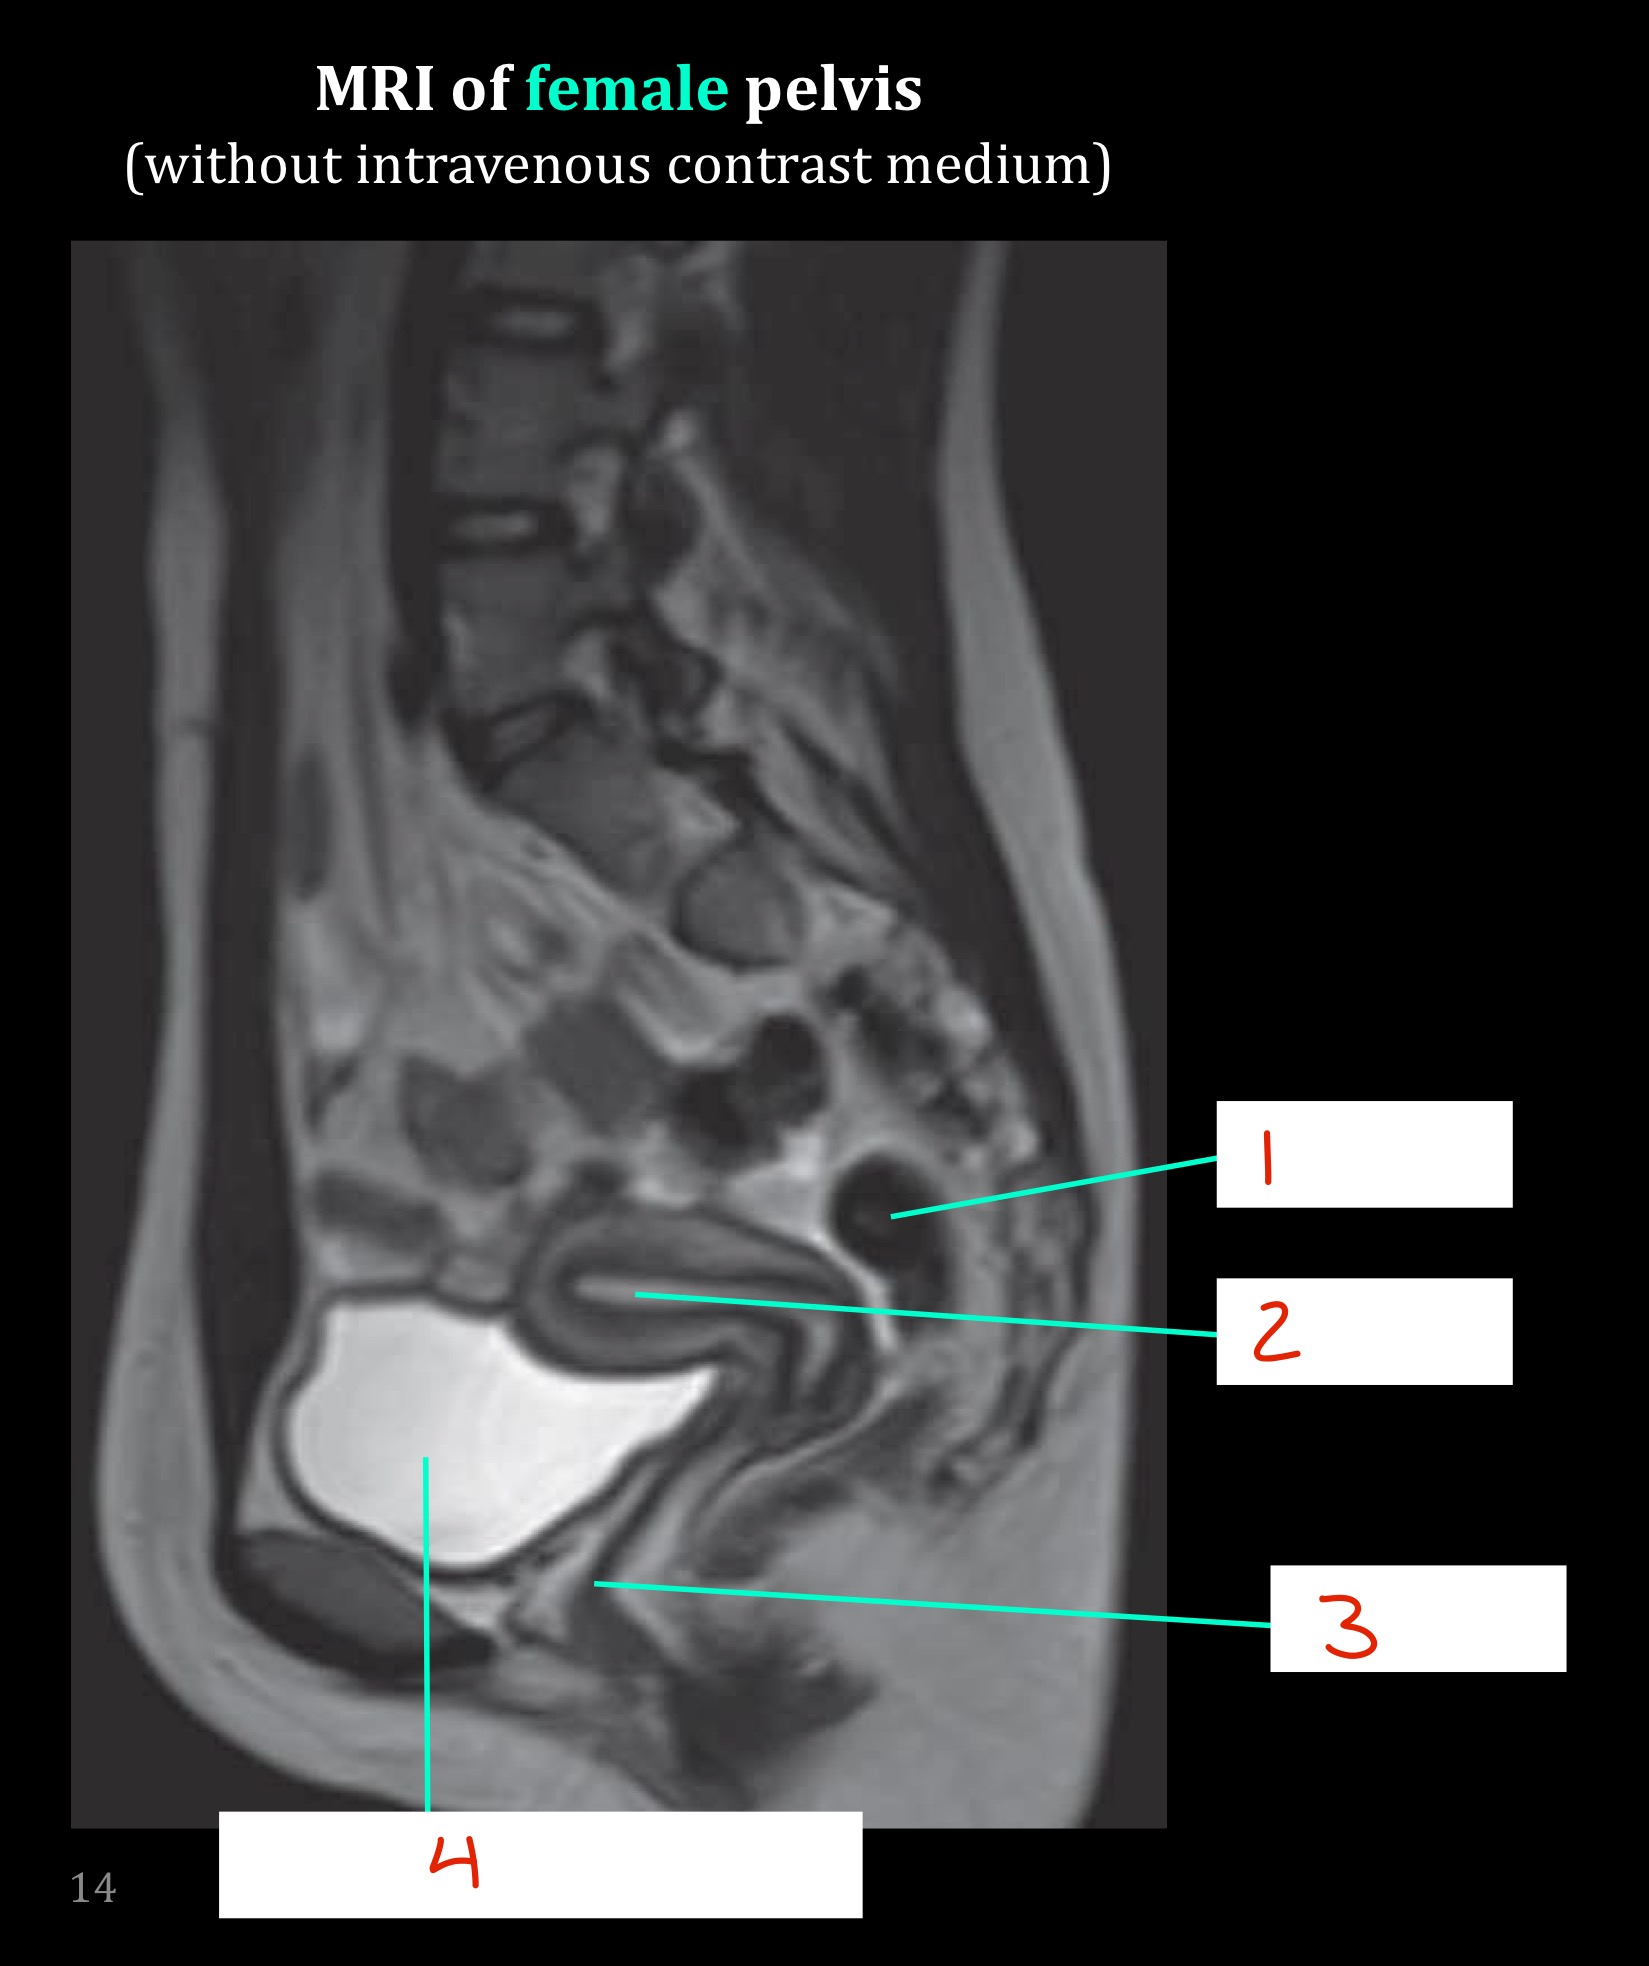

Identify

Rectum

Uterus

Vagina

Urinary bladder